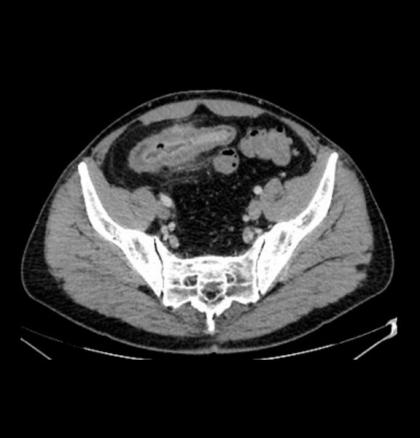

Iléite terminale avec hyperhémie muqueuse, épaississement des parois iléales, diminution de la lumière iléale et infiltration de la graisse adjacente.